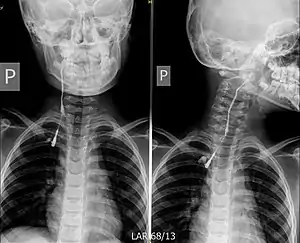

![]() Фістулографія кісти зябрової дуги праворуч. Фістулографія кісти зябрової дуги праворуч. | |